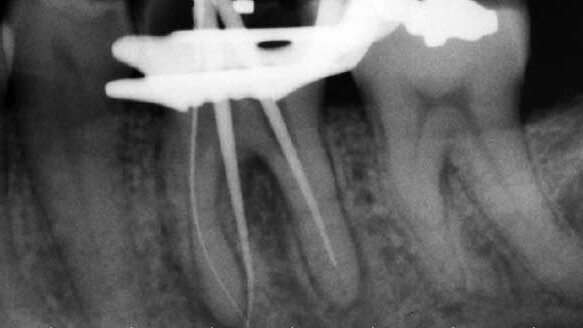

The tooth had a slightly widened periodontal ligament space (pdl), and there was some minor furcation involvement. The decay was within 1-2 mm of the mesial pulp horn. The mesial root had ambiguous anatomy. I was not able to follow the canals to the apex. In addition, it appeared that there might be three canals on the mesial root.

Because I had a good pretreatment image, I measured the canals with a digital apex locator. In addition, the patient had a very severe gag reflex that was exacerbated when we placed a sensor in his mouth to take a digital image. Clinically, it is imperative to have both a digital image and results via apex locators. Due to his gag reflex, I opted to go with only an apex locator reading.

Once I was able to quantify the canal lengths, I shaped all five canals with TF rotary nickel titanium instruments (Sybron Dental Specialties) (Fig. 3). Once I finished shaping, I took a trial cone image and was surprised to see that I perforated a mesial root where I suspected there to be a middle mesial canal (Fig. 4).

Second, I deferred to my digital apex locator to verify canal lengths instead of taking a digital image to verify all of the canals and to verify that I had indeed found a middle mesial canal. Had I done that, I would have realized that I had a minor perforation and would have easily been able to repair the minimal invasion of the furcation area. Instead I relied on my “file flick” test to confirm that I was in the canal. Ironically, the perforation did not bleed very much at all through my entire sequence of shaping with RNT files.